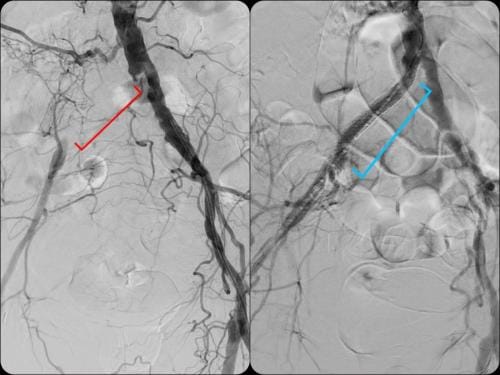

During these procedures: Sedation is given to help you relax. Next, a tiny tube is gently inserted in an artery, usually in the groin or upper thigh area. You will be given a local anesthetic to numb the area where the tube will be inserted. It is then guided through the blood vessel toward the disease artery. When it’s in place, a dye is injected through the catheter to visualize the arteries. An X-ray is taken to help the physician pinpoint the area that is blocked or narrowed. The physician then uses tiny wires and catheters to get through the diseased vessels. Depending on the images treatment may then be performed.

Angioplasty — a special catheter that has a balloon on one end is advanced into the diseased artery. This is temporarily inserted through the narrowed artery and inflated to flatten the plaque against the artery wall, opening the artery and restoring blood flow.

Stent placement —a stent is a small, expandable, leg pain angioplasty stent los Angeles san diegomesh-like tube that supports the artery and helps to keep it open. Implanting a stent does not require open surgery. The doctor inserts a catheter into an artery in your arm or leg, similar to the balloon angioplasty procedure. A specially designed catheter delivers the stent to the narrow area in the artery. The stent is expanded, flattening the plaque against the artery wall and holding the artery open with a mesh tube. The catheter used to deliver the stent is then removed, but the stent stays in your artery permanently to maintain healthy blood flow.

Atherectomy — a specialized catheter that modifies the plaque in the arteries. Unlike angioplasty and stenting, which are designed to move plaque to the sides, atherectomy involves cutting and removing or sanding down the plaque from the artery, restoring normal blood flow.

Superior catheter and wire skills is essential in a delicate procedure such as treating blocked arteries. We treat a number of patients that have had failures by other specialists. Our doctor is an image-guided specialist having performed over 5,000 procedures with successful experience in venous and arterial blockages. Having a wide array of experience in different image-guided procedures brings a unique skill set to ensure that you have the most successful outcome without complication. Rest assured that our specialist can not only complete simple procedures like other centers, but he has a consistent history of successfully treating complex cases.

We have a high success rate at CVI not only because our physician is expertly skilled but also because we provide the physician with the best tools needed to open the blocked vessels. The choice of wires and catheters that are placed through the vasculature are essential to provide the best chance at success. Unlike other clinics you can rest assured that at CVI we do not cut corners and only purchase the best and highest quality tools that our specialist requires.